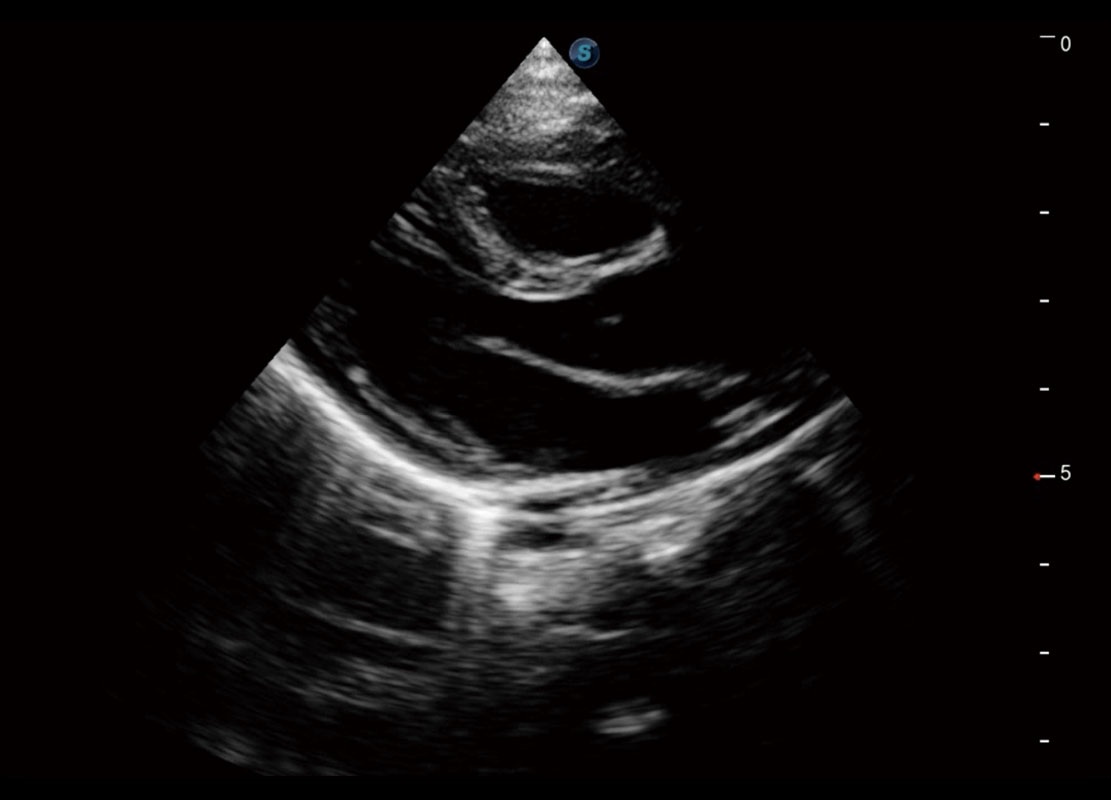

胎心筛查

P60搭载一系列胎儿心脏成像技术,实现精细的胎儿心脏评估。

• 四腔切面